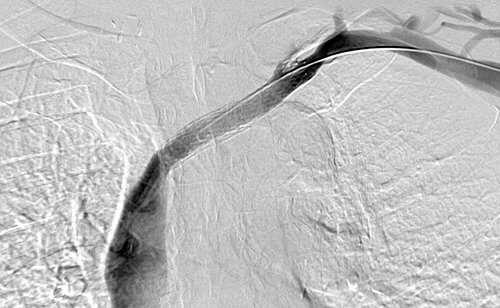

35 year old male patient with CKD requiring hemodialysis via a LUE AV graft. He presents with left upper extremity swelling secondary to a left brachiocephalic vein occlusion.

Comment: This chronic occlusion was treated with stent placement. Unfortunately, the stent occluded within months of placement, necessitating placement of additional stents. This happened again a few months later, requiring angioplasty and covered stent placement.